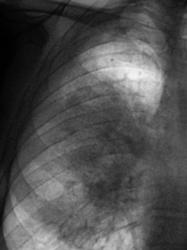

Через 2 недели после проведенной противовоспалительной терапии пациент чувствует себя хорошо, "стоит" вопрос о выписке из стационара. Проведено контрольное рентгенологическое исследование в стандартных проекциях.

Отличное наблюдение, Валентин Львович! За что боролись, на то и напоролись. Пусть коллеги терапевты вкупе с фтизиатрами попробуют это вылечить! С такой диссиминацией очень сложно и долго необходимо бороться.

Вызвал больного для производства томографии. Произвели исследование и "выпали в осадок". Действительно "Все хорошо".

Ну вот! Плюс деструкция легочной ткани! Случай довольно тяжелый!